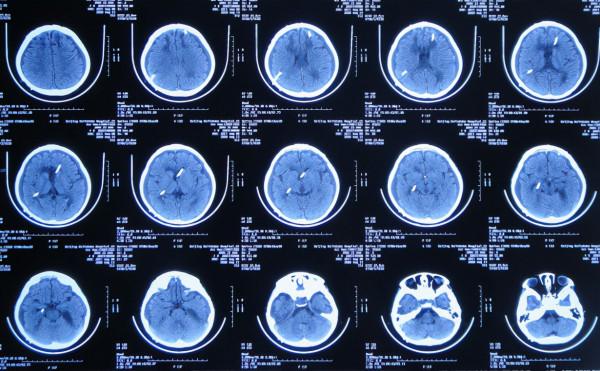

患兒於2019年12月5日下午,出現發熱,家屬自行給予口服布洛芬混懸液治療,但2019年12月6日凌晨2點左右,患兒睡眠中喊頭痛,家屬開車急送至安徽省蕪湖市弋磯山某三甲醫院,去醫院途中病情變重患兒呼之不應;到院後急診查頭部增強CT示蛛網膜下腔出血(圖-1),考慮血管畸形,於凌晨4點急診進行了腦室外引流術;術後當天早晨8點進行了DSA檢查排除血管畸形(圖-2)。

圖-1:2019年12月6日頭部增強CT